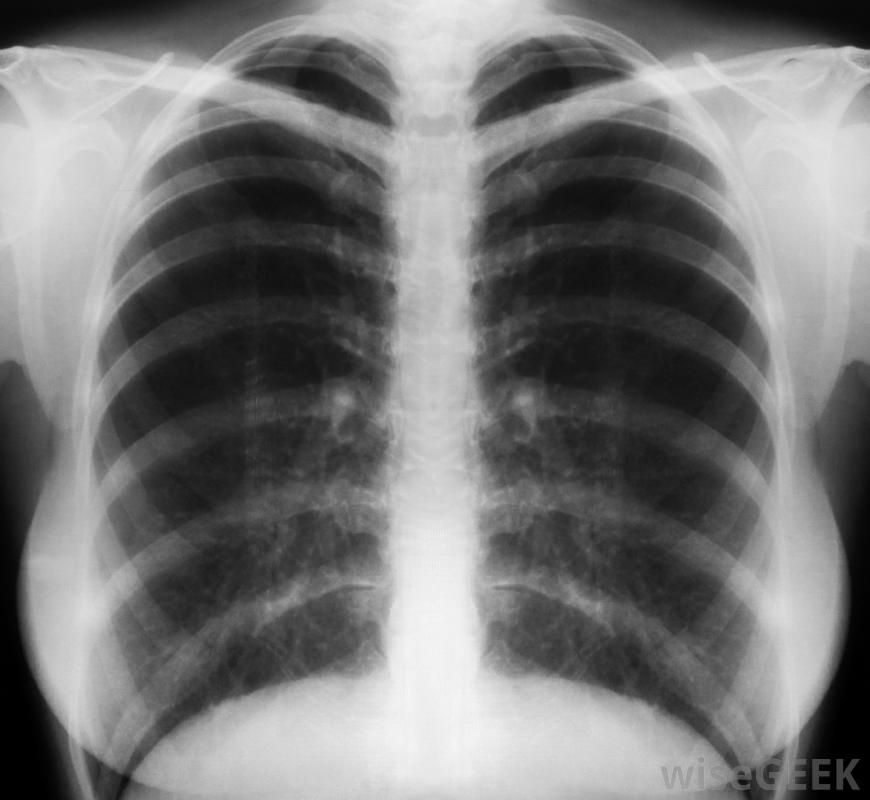

哮喘患者也会成为某些过敏症的受害者,医生可以通过进行一系列的诊断试验。医生用听诊器听病人的胸部,并指导他向一种称为峰值流速计的装置吹气以测量肺活量。经常进行胸部x光检查,以便医生更好地评估炎症和气道阻塞的严重性

经常使用胸部x光片,这样医生可以更好地评估哮喘的严重性慢性过敏可导致哮喘